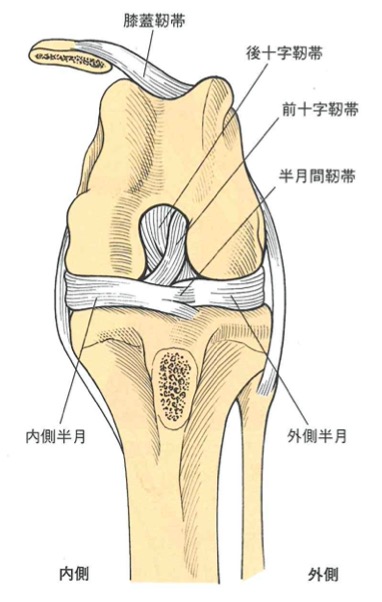

前十字靭帯は膝関節内に存在する大腿骨の尾側と脛骨の頭側を繋ぎ、前方から見ると外側から内側へと走行している靭帯です。

この構造から前十字靭帯は膝関節の過度な伸展の防止、脛骨の前方突出と過度な内旋を抑制する役割を担っていますが、膝関節を過度に伸展や内旋する外的な力が加わることで前十字靭帯断裂を引き起こします。

膝関節の構造(引用:スモールアニマル・サージェリー 第3版p.1407)